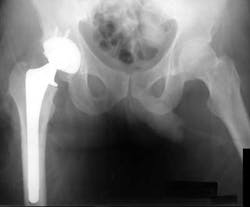

Arthroplasty is a surgical procedure to restore the integrity and function of a joint. Biofilms are an important consideration in the pathogenesis of prosthetic joint infections.(3) Organisms within biofilm become resistant to therapy, and as a result, antimicrobial therapy is often unsuccessful unless the biofilm is physically disrupted or removed by surgical debridement. This is similar to biofilm in the oral cavity, and we always perform debridement whether or not we use an antimicrobial.